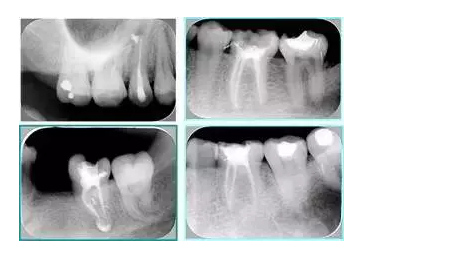

左圖和上圖為干髓治療后牙齒,齲齒疏通后進(jìn)行根管充填。

如圖為塑化加根充處理后牙齒 X 線片。

6. 鈣化

常見有修復(fù)性鈣化和增齡性鈣化。下面為根管鈣化 X 線片。